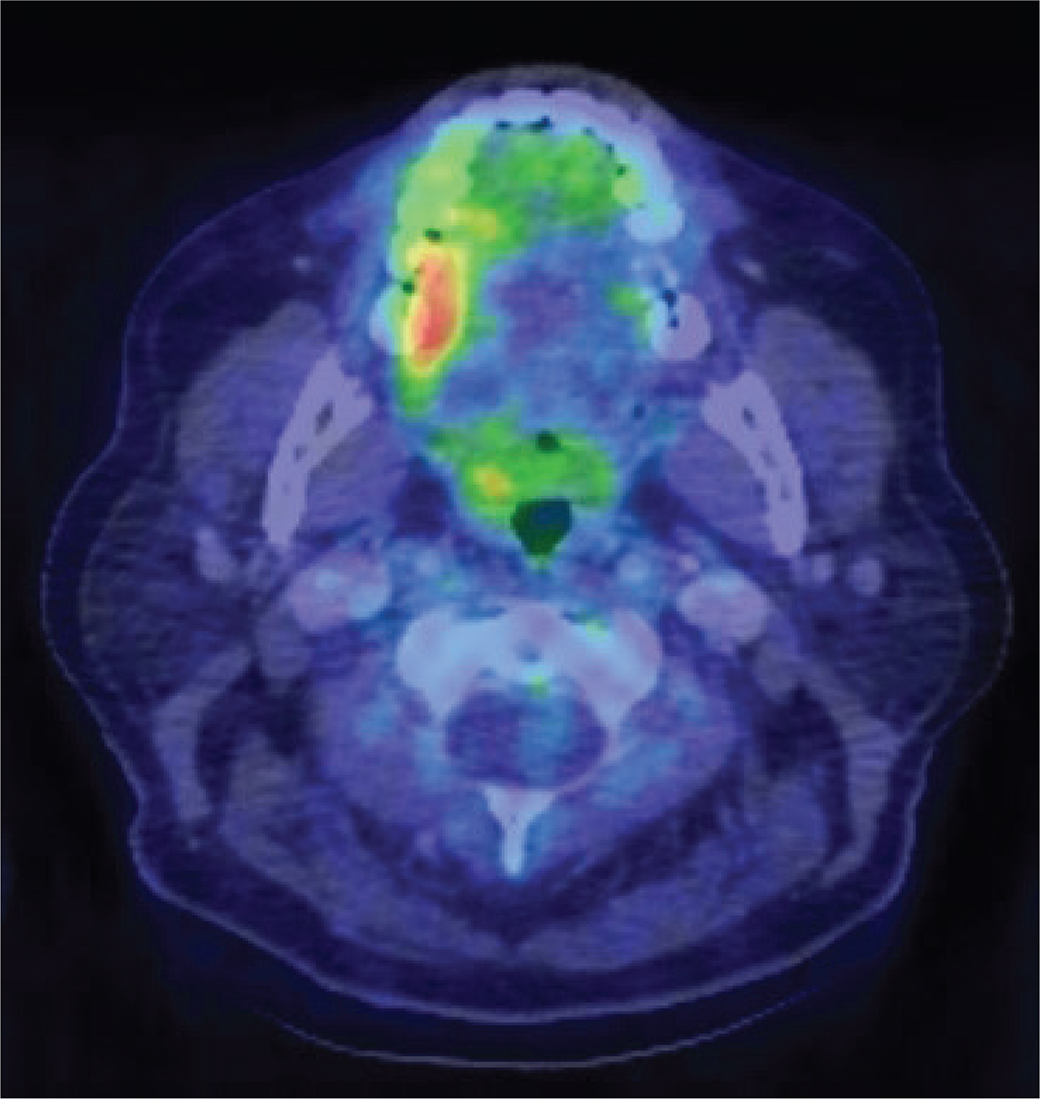

In August 2018, 6 months after the latest excision biopsy of the lesion, the patient underwent fluoro-deoxy-glucose positron emission tomography with computerized tomography (FDG PET/CT) for evaluation and diagnosis of IgG4-RD. This method enabled an individually tailored treatment and provided a better understanding of the disease (37). FDG PET/CT showed involvement of multiple groups of lymph nodes in the mediastinum and neck. There was also an increased uptake on the right side of the mouth, directly corresponding to the right side of the tongue and cheek (Figure 10). A neck lymph node biopsy demonstrated elevated levels of IgG4-positive plasma cells, displaying an IgG4+ plasma cells/HPF of 10–50 and an IgG4+/IgG+ ratio of ≥71%. This further strengthened our suspicions of IgG4-RD.

Fig 9

Figure 10. FDG PET/CT showing an increased uptake on the right side of the mouth corresponding to the right side of the tongue and cheek.